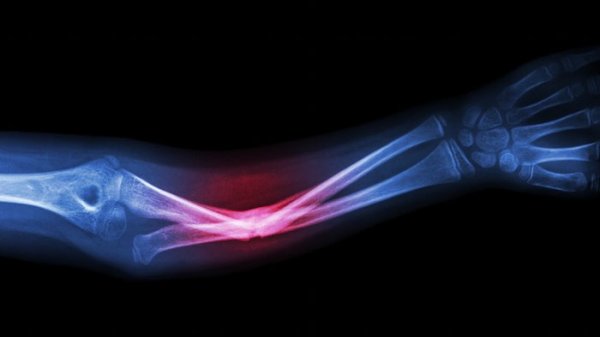

新的技术抛弃了使用外源细胞或者分子来做修补和让受损骨骼组织重新生长,而是使用了聚合物纳米壳,一种放置于体内的微型胶囊,可以把微小RNA分子送到损伤处。当纳米壳开始分解时,微小RNA分子就被释放出来,指挥周围的细胞“激活”天然的造骨和愈合机制。有点像项目经理在拆迁现场,指挥建筑工人重建房屋一样。

这个新技术有两点关键优势。一、纳米壳是设计为缓慢分解的,这样可以逐渐释放微小RNA分子,因此恢复性治疗可以触须一个月或者更久。二、这个过程使用人类自己的细胞,而不是引入外源修复中介,就避免了细胞排斥或者跟损伤有关的肿瘤。

这很重要,因为理论上说,我们的骨头本身就含有一切可以保持健康强壮的成分,但是愈合过程却并非在需要的时候可以激活,因此才会有持续损伤,蛀牙或者骨质疏松。把管理愈合过程的任务交给微小RNA,研究者们希望修复工作可以做到持续和彻底。

虽然这项技术只在老鼠身上试验过,但它很有希望对人类也有用,这也是研究者下一步的打算。最终,这种自愈治疗将会用来等待骨科手术或者关节修复,甚至龋齿修复(Ma自己就是一名牙医学教授)。

在专门目的下生长和再生高质量的骨骼一直是个充满挑战的难题,因此密歇根大学的新发现充满了潜力。实验中使用的老鼠患有骨质疏松,在欧洲,美国和日本有近7500万骨质疏松患者,这些人的生活将会因为这项技术得到改善。